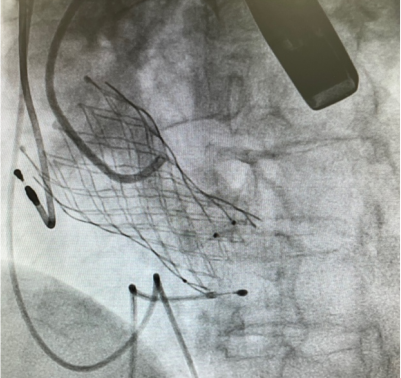

瓣膜完成釋放

經過術前的精確評估,在多學科團隊協同下,姚啟恆教授團隊為曾阿姨實施了TAVR手術。術中的精準操作,瓣膜釋放定位及膨脹形態良好,研判後決定不行煙囪支架,避免了冠脈支架的植入。術後測得即刻跨瓣壓差降至10mmHg以內,效果滿意,順利解決了曾阿姨「心口難開」的頑疾。

姚啟恆教授介紹說:「術前評估患者瓣葉明顯增厚,左右冠竇部分粘連,法式竇結構不大。術中左冠開口閉塞高風險,團隊預先行冠脈保護,主動脈弓降部走行接近直角,過弓可能遇到其他意外困難,很考驗術中精準操作。」

姚啟恆教授團隊為曾阿姨進行手術